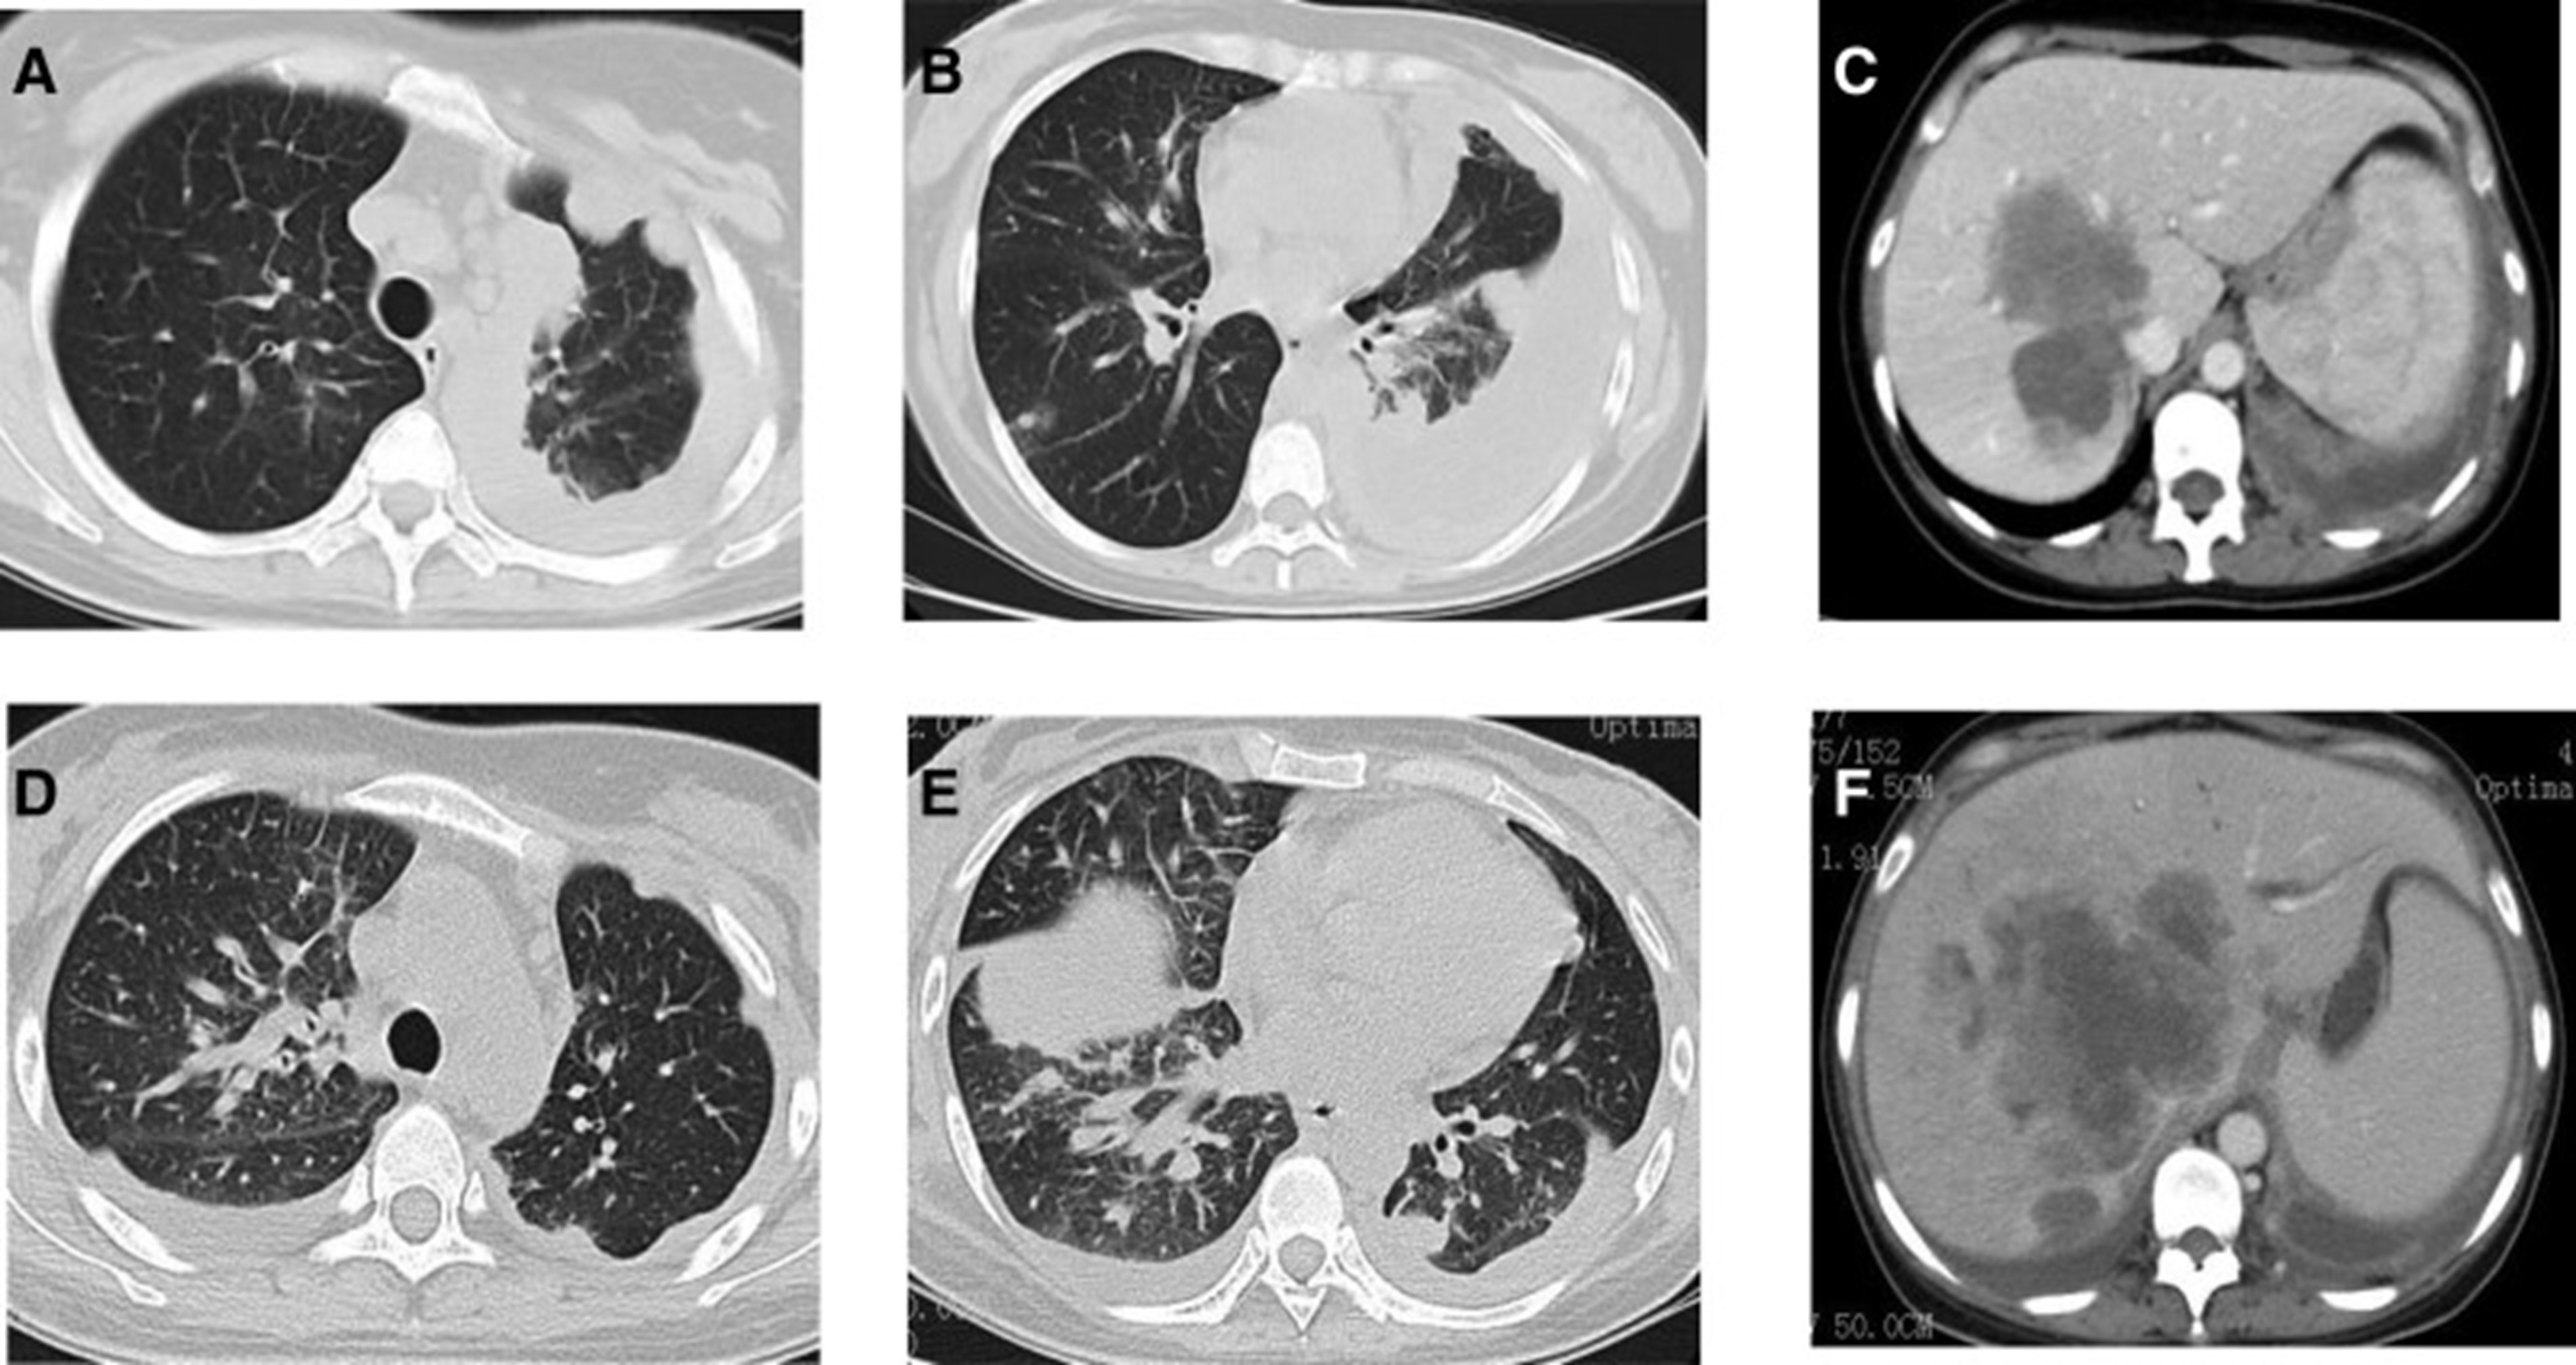

1个月后复查显示肺部和肝内病变进展(图1)。(图 6A-C)(根据RECIST1.1),她的抗肿瘤治疗改为“培姆曲塞加卡铂和贝伐单抗”的治疗一个周期。2020年12月至2021年1月,再次改变患者的治疗方案,这次改为“劳拉替尼联合达拉非尼”靶向治疗。使用 PD 联合胸部和腹部 CT 评估疗效(图 1)。(图 6D-F)(根据 RECIST1.1)。患者无法耐受化疗、靶向治疗、IO 治疗或任何其他积极的抗肿瘤治疗。这是因为患者的一般情况较差,包括发烧、腹痛和胆红素水平升高等症状。随后,给予患者静脉营养、镇痛等对症支持治疗。患者于 2021 年 2 月 4 日去世,总生存期(OS)为 10 个月。

和 2022 年 1 月 (D-F) 的 CT 扫描.jpg)

图 6:2020 年 11 月 (A-C) 和 2022 年 1 月 (D-F) 的 CT 扫描。CT = 计算机断层扫描。